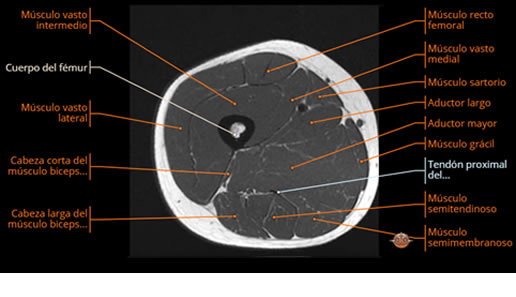

Se realiza estudio de MRI de muslo izquierdo en diferentes planos, con secuencias de Spin Echo, GRE; ponderadas a T1 y a T2, se utilizan pulsos de saturación de grasa y se administra medio de contraste IV a base de Gadolinio en base al peso del paciente.

La diáfisis femoral izquierda muestra reacción perióstica importante, se extiende desde el cuello del fémur, invade trocánteres, diáfisis femoral, medial y distal, es compatible con un proceso infeccioso óseo, el complejo muscular del muslo se ve edematizado.

La resonancia es la modalidad de elección para valorar la extensión intramedular y la infiltración en tejidos blandos, brindando una imagen más detallada del compromiso tumoral. Los hallazgos característicos incluyen:

Lesión de señal heterogénea en secuencias T1 (hipointensa) y T2/STIR (hiperintensa), que refleja necrosis, hemorragia y contenido celular diverso.

Compromiso de la médula ósea adyacente y de estructuras vecinas, como músculos y neurovasculatura.